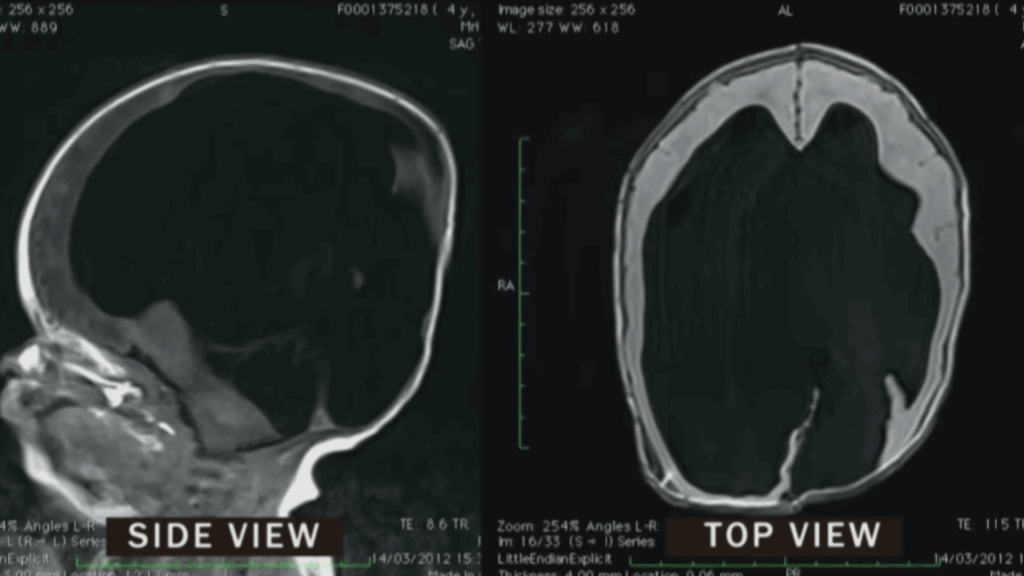

The Shocking MRI Results

An MRI scan shortly after birth revealed stunning news. Noah was actually born with just two percent of his physical brain. This was far worse than doctors had anticipated. A thin layer of brain tissue existed only at the front of his head. The porencephalic cyst had destroyed most of his developing brain. Medical staff prepared his parents for a vegetative state existence.

Within three years, Noah’s brain remarkably grew from two percent to 80 percent. Scientists believe his brain tissue was compressed rather than absent. The shunt allowed room for his brain to expand properly. Noah began responding to environmental cues in ways doctors couldn’t explain. He could see, hear, and communicate despite missing crucial brain regions. Medical professionals struggled to understand his incredible recovery.